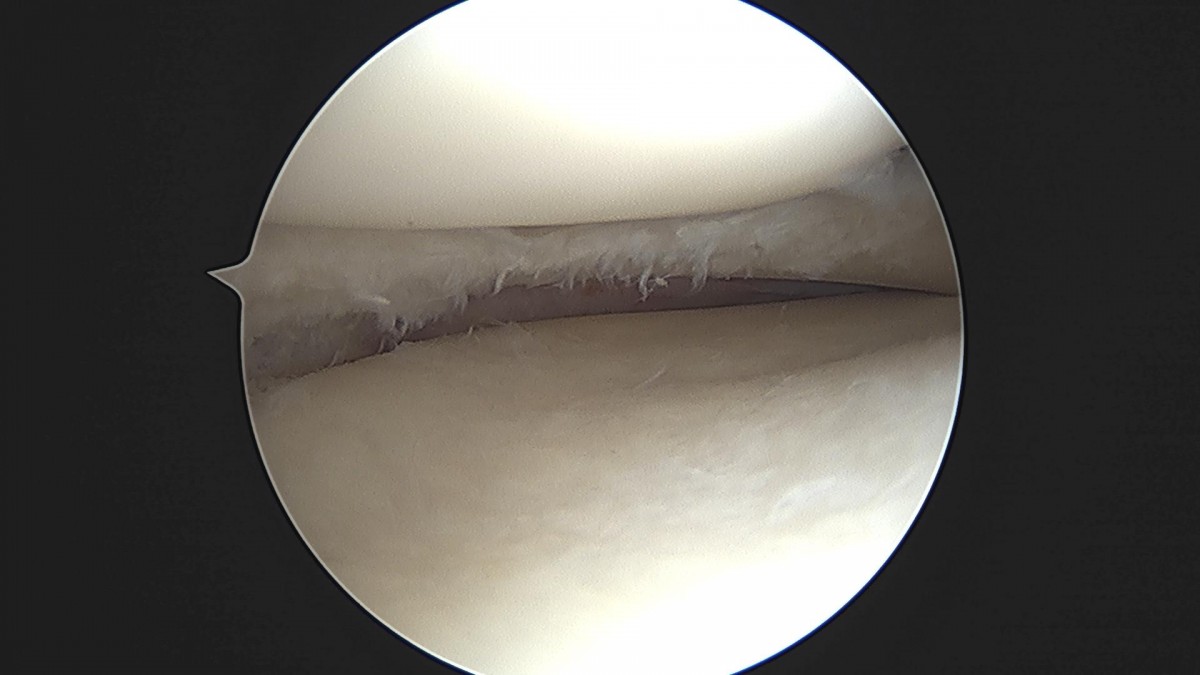

배우한원장님 무릎 반월상연골판 절제술 이관O 환자

ade708f6ffdfd2e6dcf188e7ecb45ff3_1673513854_1307.jpg